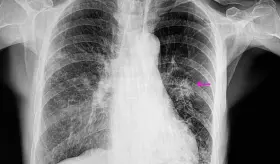

Algunos virus, pulmonía, asma y otras condiciones comparten síntomas y hasta hallazgos radiológicos, por lo que solo un especialista puede diferenciarlas con precisión.

El cáncer de pulmón debe enfrentarse con dos pilares: la prevención, que incluye reducir la exposición al tabaco, contaminantes ambientales y riesgos laborales y la detección temprana, porque es este diagnóstico precoz el que realmente salva vidas.

En la isla, más de ochocientos nuevos casos son diagnosticados anualmente, siendo el tercer cáncer más común en hombres y el quinto en mujeres, lo que subraya la urgencia de esta iniciativa.